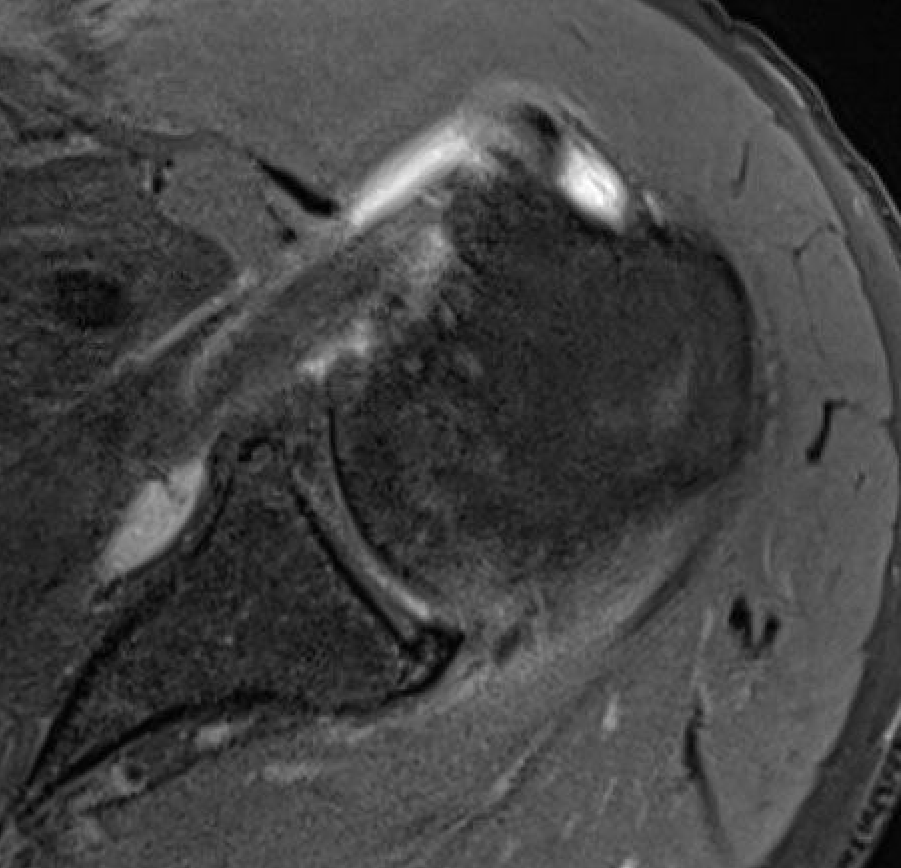

Medial subluxation with subscapularis tear